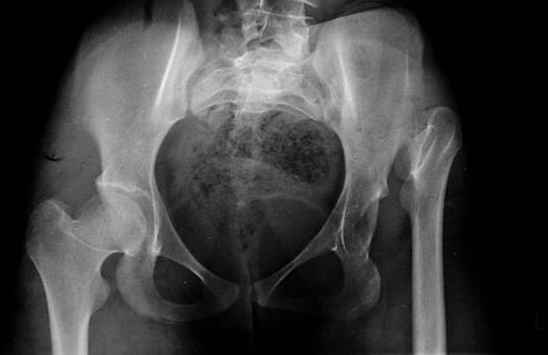

Moghno i tak kak sdelali my: pelvic support + tibial and equinus correction .

Слайд 2